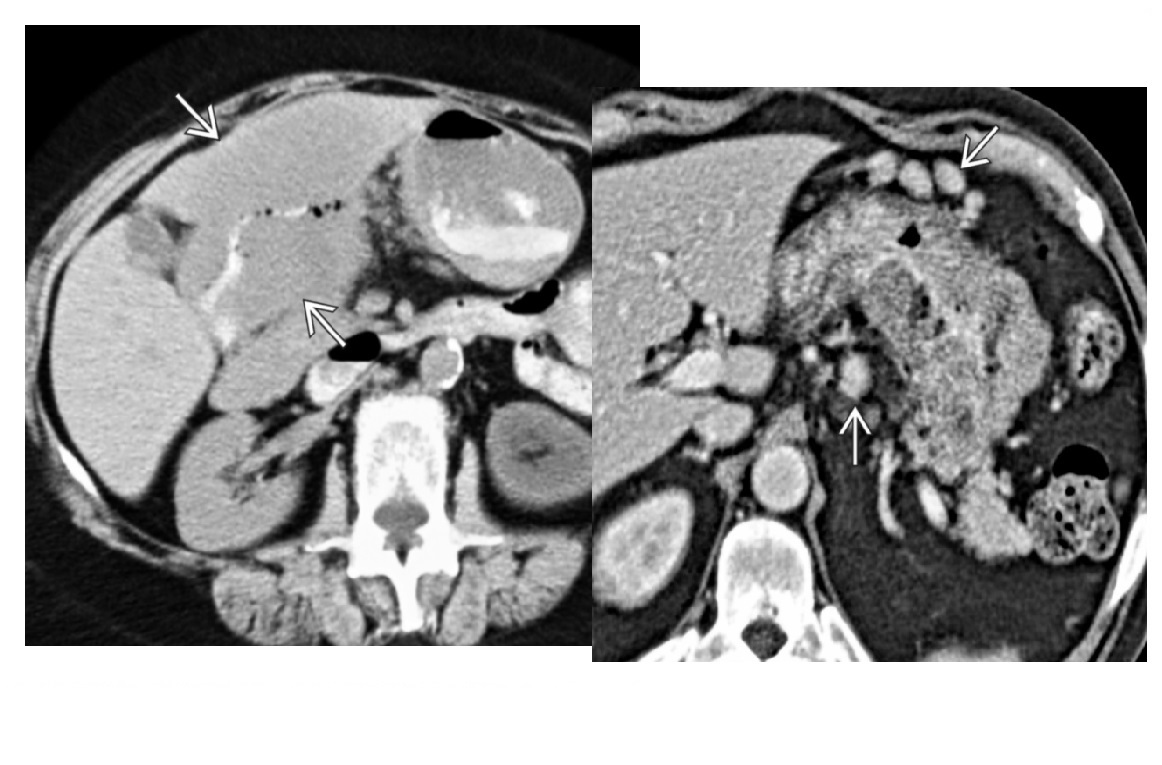

Pyogenic -Singular - Klebsiella -Multiple - E.coli **-'Double targe sign'** -Confluent complex cystic lesions Candida - Bulls eye Amoebic - 'extra hepatic extension' - if left lobe needs emergently drained as can rupture into the pericardium -transient hepatic attenuation difference (THAD) due to thrombophlebitis of portal vein and hyperemia of abscess capsule - enhancing capsule and hypodense halo of edema Hydatid - 'water lily, sandstorm' - Large, well-defined, cystic liver mass with numerous peripheral daughter cysts - Echinococcus Schistosomiasis is - 'Tortoise shell' - Septations hyperdense